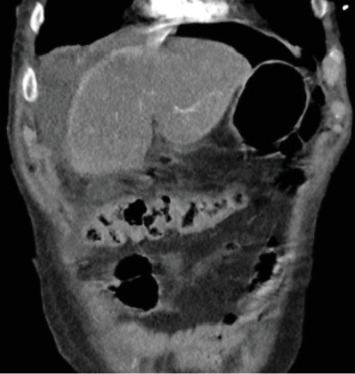

Peptic ulcer disease (PUD) results from erosion and ulceration of the upper digestive tract mucosa. Clinical presentations can vary from asymptomatic to severe complications such as perforation, strictures, or bleeding. Perforation can release enteric contents and gas into the abdomen, leading to intra-abdominal sepsis, requiring surgical intervention for source control and repair. We present a case of a 69-year-old male who developed both Fournier's gangrene and a right-sided pneumothorax secondary to a nontraumatic perforated duodenal ulcer. The patient underwent an emergent thoracostomy, laparotomy with Graham omentoplasty, and extensive debridement with successful outcome. While rare complications like pneumothorax and necrotizing soft tissue infections have been documented, their simultaneous occurrence from a nontraumatic ulcer perforation is unprecedented in literature. Previous reports suggest enteric contents can traverse retroperitoneal fascial planes and peritoneal defects to reach distant anatomical sites as a possible mechanism for these complications. This case highlights the potential for atypical presentations of PUD and the importance of comprehensive evaluation, early recognition, and prompt surgical intervention.